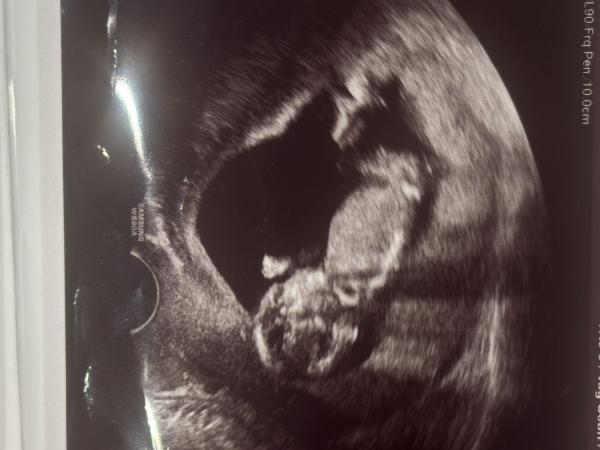

Hallo ihr lieben,  ich bin ungeduldig und frage mich, ob es hier ein paar nun-Theorie Kenner gibt die mir sagen/schätzen können was es wird Smiley nr103.gif das Bild ist aus Woche 13+0

Bild zu Nub-Theorie Experten: Mädchen oder Junge? - Schwanger - wer noch? Rund um die Schwangerschaft

Also ein Experte bin ich nicht. Wenn man am Ende deines Bildes den Nub sieht hinter den Beinen, dann steht er ab und es deutet auf Junge hin. Ich bin mit aber ehrlich gesagt nicht sicher.  Vielleicht meldet sich ja noch jemand anderes dazu.

Bin da voll bei Miramar, der Nub steht wirklich weit hoch. Würde auch auf einen Jungen setzen 😊

Ihr hattet recht, es wird ein Junge!